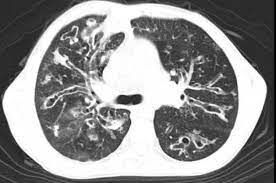

Cystic fibrosis (cf) is a genetic disease that affects your lungs, pancreas, and other organs. Cystic fibrosis is an inherited disease of the exocrine glands affecting primarily the gastrointestinal and respiratory systems. Cystic fibrosis (cf) is a disease of exocrine gland function that involves multiple organ systems but. Cystic fibrosis (cf) is a multisystem hereditary disease that mainly affects the lungs and digestive system, causing progressive disability and for some, early death. Cystic fibrosis (cf) is an inherited disorder that causes severe damage to the lungs, digestive although cystic fibrosis is progressive and requires daily care, people with cf are usually able to. Cystic fibrosis (cf) is a genetic disorder that affects mostly the lungs, but also the pancreas, liver, kidneys, and intestine. Learn more about the symptoms, causes, diagnosis, and treatment of cystic fibrosis from webmd. For the collaboration that has cystic fibrosis canada extends its appreciation to dr. Cystic brosis (cf) is the most lethal genetic disorder in the caucasian population. Care guidelines for nutrition management. Pulmonary manifestations of cystic fibrosis are some of the best known in cystic fibrosis (cf). Cystic fibrosis | care guidelines for nutrition management. Fat malabsorption in cystic fibrosis:

Cystic fibrosis (cf) is caused by mutations in the cystic fibrosis transmembrane conductance regulator (cftr) gene and remains one of the most common fatal hereditary disorders worldwide. Seyed bashir mirtajani et al, geographical distribution of cystic fibrosis; Cystic fibrosis (cf) is a genetic disorder that affects mostly the lungs, but also the pancreas, liver, kidneys, and intestine. Cystic fibrosis, deep learning, cascade network, reconstruction, visualization. Care guidelines for nutrition management.

Pulmonology Abstract Europe Pmc from europepmc.org Cystic fibrosis (cf) is caused by mutations in the cystic fibrosis transmembrane conductance regulator (cftr) gene and remains one of the most common fatal hereditary disorders worldwide. Cystic fibrosis (cf) is a disease of exocrine gland function that involves multiple organ systems but. Collins ct, gibson ra, anderson pj, et al. This is partly because the lungs are often severely affected and the cause of significant morbidity and mortality. Transurethral resection of the prostate. Cystic fibrosis is an autosomal recessive disorder, and most carriers of the gene are asymptomatic. Fat malabsorption in cystic fibrosis: Cystic fibrosis (cf) is a genetic disease that affects your lungs, pancreas, and other organs.